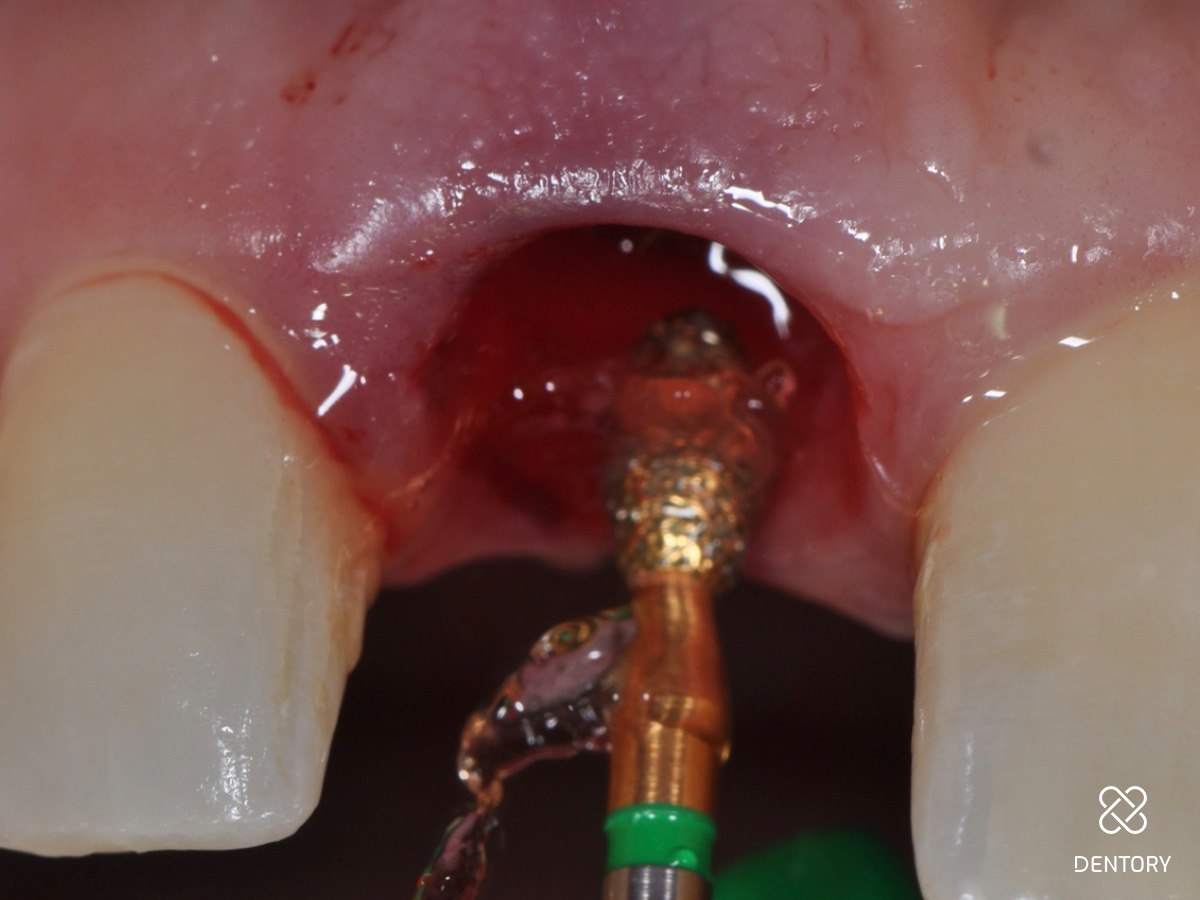

Abbildung 7

Okklusale Ansicht der Extraktionsalveole. Die Entfernung des Saumepithels erfolgt mit einem grobkörnigen Diamantbohrer.

Abbildung 8

Das Saumepithel wurde entfernt und eine Blutung ausgelöst.